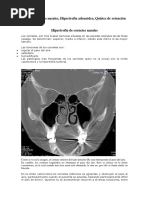

La Rinitis se define como la inflamación de las estructuras del interior de la nariz

llamadas cornetes que ocasiona molestias al paciente de tipo obstrucción nasal y

falta de respiración por la nariz, rinorrea o salida de secreción transparente

abundante por una o ambas fosas nasales, picor nasal y de garganta, estornudos

repetitivos

Cornetes Cornete nasal superior (del hueso

etmoides)

Cornete nasal medio (del hueso

Cornete nasal inferior (hueso

independiente)

Espacios Receso esfenoetmoidal

Meato nasal superior

Meato nasal medio

Meato nasal inferior

Meato nasal común

Funciones Calentar y humidificar el aire, proteger y

drenar los senos y celdillas paranasales